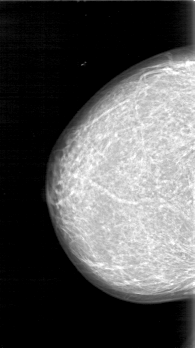

D_4026_1.RIGHT_MLO

RIGHT_MLO LINES 5281 PIXELS_PER_LINE 3031 BITS_PER_PIXEL 12 RESOLUTION 43.5 NON_OVERLAY